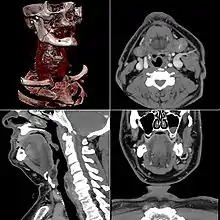

Dans les appareils modernes, l'émetteur de rayons X (tube à rayons X) effectue une rotation autour du patient en même temps que les récepteurs situés en face, et qui ont pour fonction de mesurer l'intensité des rayons après qu'ils ont été partiellement absorbés durant leur passage à travers le corps. Les données obtenues sont ensuite traitées par ordinateur, ce qui permet de recomposer des vues en coupes bidimensionnelles puis des vues en trois dimensions des organes. On peut faire ressortir le contraste de certains tissus, en particulier des vaisseaux sanguins, en injectant un produit dit « de contraste » (un complexe de l'iode) qui a la propriété de fortement absorber les rayons X et donc de rendre très visibles les tissus où ce produit est présent (qui apparaissent alors hyperdenses, c'est-à-dire plus « blancs » sur l'image). Grâce aux tomodensitomètres multidétecteurs (ou multi-barrettes) à acquisition spiralée (déplacement lent de la table d'examen durant l'acquisition), on obtient depuis les années 1990 une exploration très précise d'un large volume du corps humain pour un temps d'acquisition de quelques secondes.

Celles-ci se présentent sous la forme de « coupes » ou tranches d'épaisseur millimétrique (de 0,4 mm à 10 mm) que le radiologue peut étudier dans tous les plans de l'espace (sagittal, axial, coronal et obliques), et qu'il s'agit de post-traiter (augmentation de l'épaisseur des coupes visualisées, mise en valeur de certaines densités, reconstructions volumiques en 3D, extraction des vaisseaux ou des structures osseuses, navigation virtuelle endoscopique, etc.).